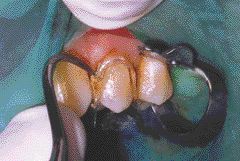

General Dentistry: Restoring Denture Abutments

FIGURE 32

As practitioners of general dentistry, restoring denture abutment teeth is a necessity. With the aging of the general population this type of procedure will be more and more common in our daily treatment schedule. The challenge of restoring a denture abutment tooth is the fit of the existing denture afterwards. Most patients can readily tell … Read more